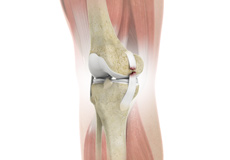

Patellofemoral Knee Replacement

Traditionally, a patient with only one compartment of knee arthritis would undergo a total knee replacement surgery. Patellofemoral knee replacement is a minimally invasive surgical option that preserves the knee parts not damaged by arthritis as well as the stabilizing anterior and posterior cruciate ligaments, ACL and PCL.